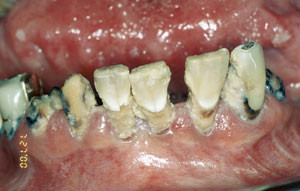

Det er velkjent at strålebehandling mot kreft i hode-hals-regionen gir orale komplikasjoner både på kort og på lang sikt (fig 1). Foreløpig er det ingen konsensus når det gjelder langtidseffekter etter cytostatikabehandling. Litteraturen på området er sparsom, men det er hevdet at salivas kvalitet og kvantitet kan være påvirket i lang tid etter endt cytostatikaterapi (9).

Spyttkjerteldysfunksjon kan gi munntørrhet, tørre og sprukne lepper, svie og brenning i slimhinnene, angulær cheilitt, proteseproblemer, smaksforstyrrelser, vanskeligheter med å tygge, svelge og snakke, karies (fig 1), progrediering av periodontal sykdom og infeksjoner, spesielt candidiasis (9). Spyttkjerteldysfunksjon kan forverre og forlenge prosessen ved mukositt og redusere munnhulens bufferkapasitet, noe som igjen øker risikoen for karies og progrediering av periodontal sykdom. Mangel på antimikrobielle proteiner som normalt skal finnes i saliva, fører også til ytterligere risiko for utvikling av karies (8).